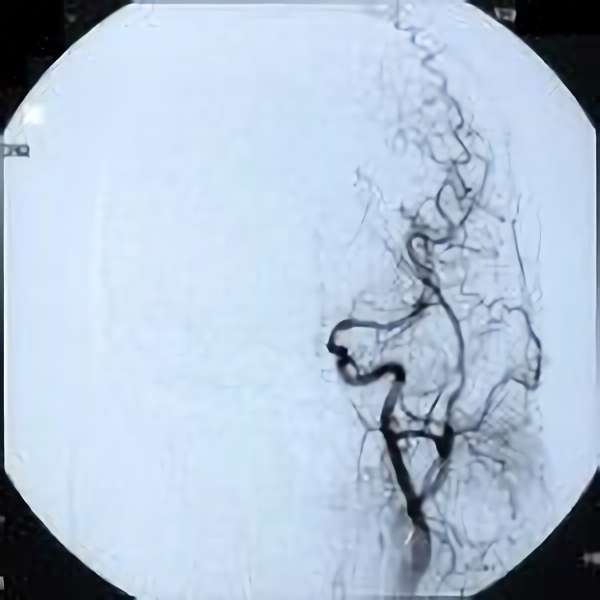

脳血管撮影

手術前

手術後